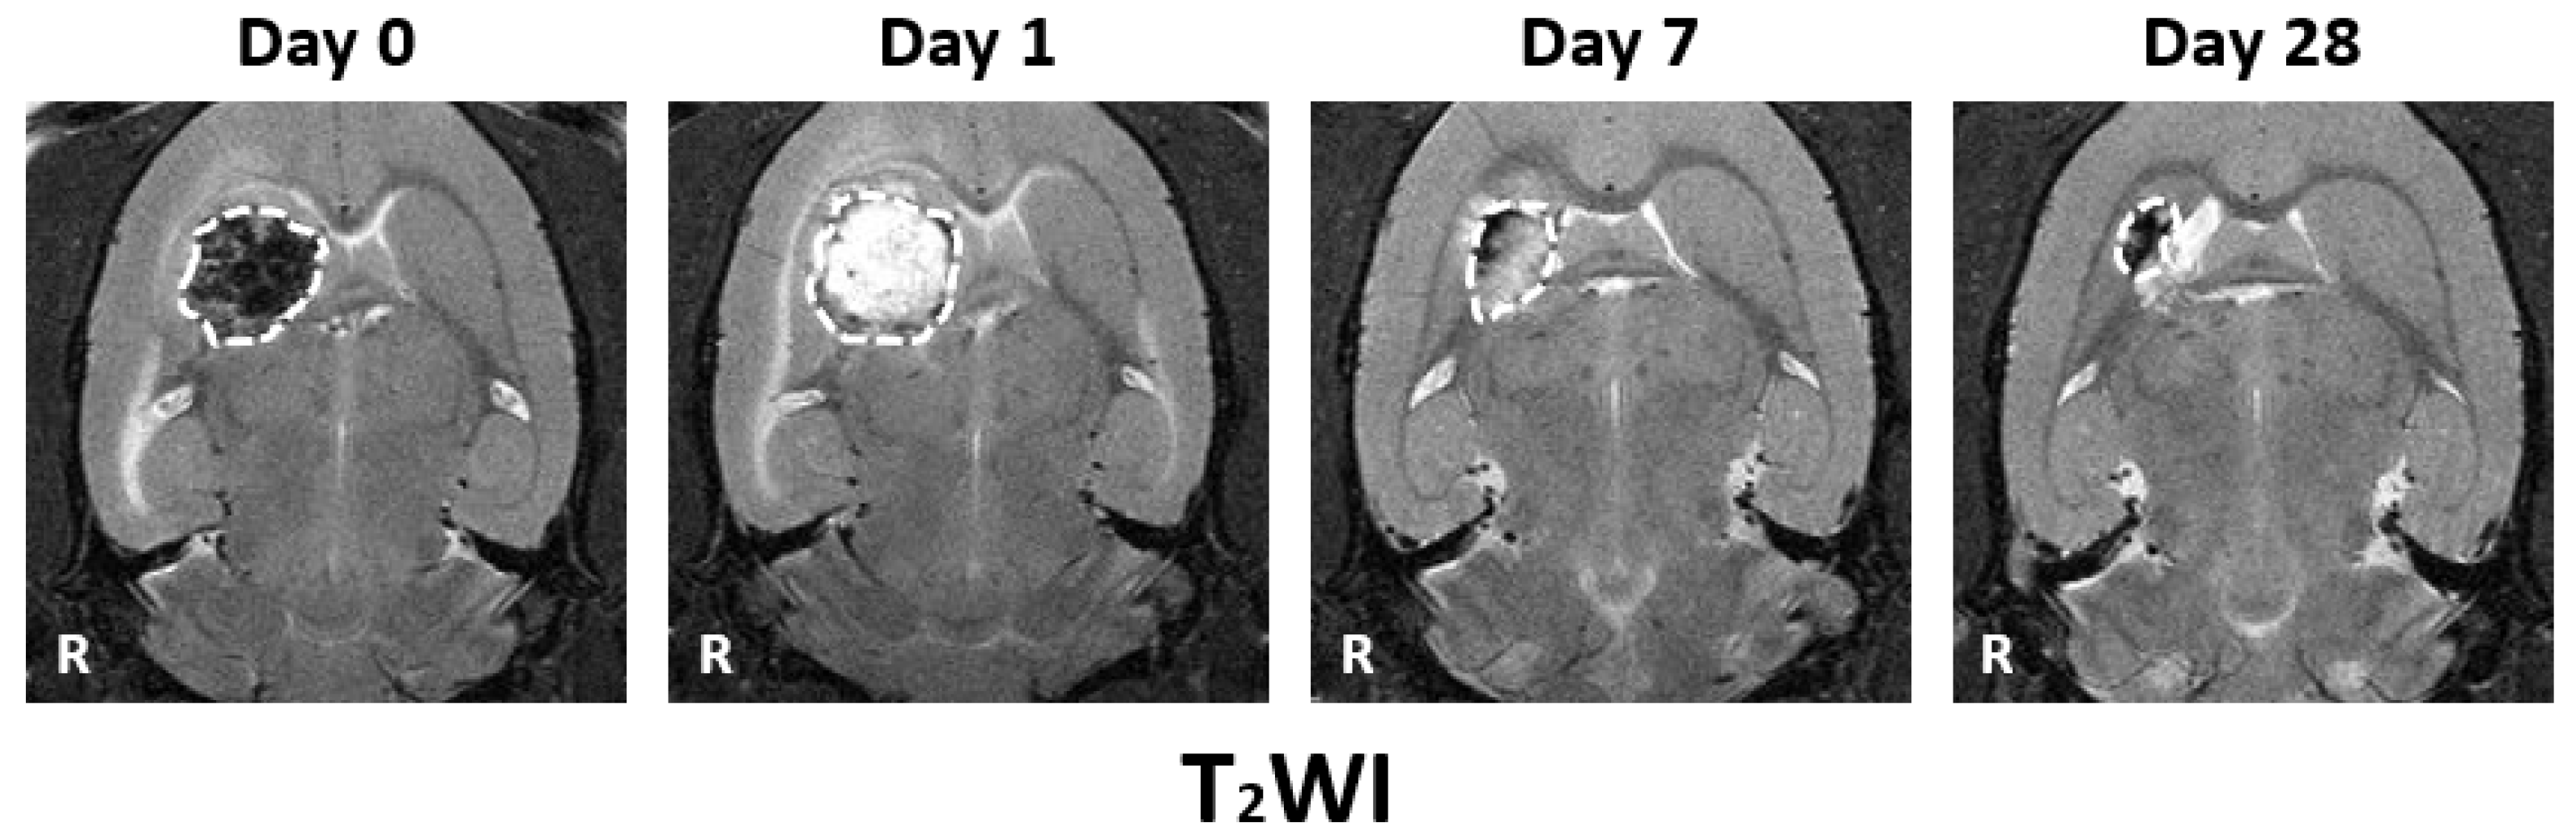

3.1. MRI Observation

3.2. Hemorrhage Signal

3.3. Hemorrhage Area